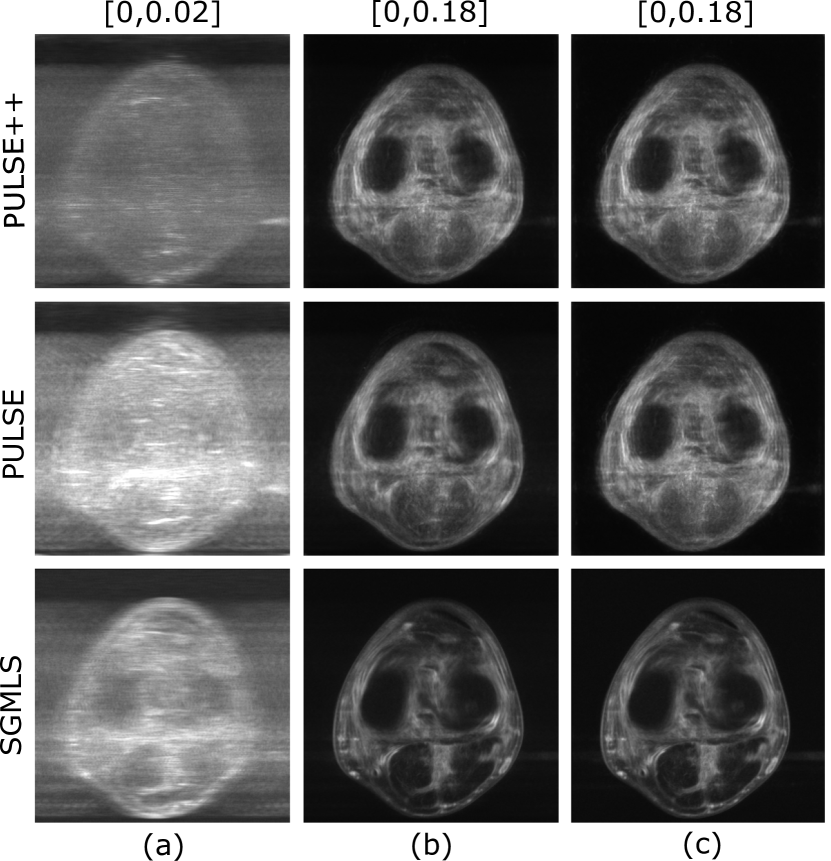

Uncertainty quantification was performed from the alternate solutions obtained with the PULSE, PULSE++ and SGMLS methods for each set of k-space data corresponding to different sampling conditions. The uncertainty map 𝐟^UMsuperscript^𝐟𝑈𝑀\hat{\mathbf{f}}^{UM} was computed as the pixel-wise standard deviation of the alternate solutions {𝐟^t}t=1Tsuperscriptsubscriptsubscript^𝐟𝑡𝑡1𝑇\{\hat{\mathbf{f}}_{t}\}_{t=1}^{T}, where T𝑇T is the number of alternate solutions. Additionally, uncertainty maps were computed separately for the measurable and null space components [27] of the alternate solutions. The measurable and null space component of an object 𝐟N𝐟superscript𝑁\mathbf{f}\in\mathbb{R}^{N} in the domain of system matrix 𝐇𝔼M×N𝐇superscript𝔼𝑀𝑁\mathbf{H}\in\mathbb{E}^{M\times N} are defined as 𝐟meas=𝐇+𝐇𝐟subscript𝐟𝑚𝑒𝑎𝑠superscript𝐇𝐇𝐟\mathbf{f}_{meas}=\mathbf{H}^{+}\mathbf{H}\mathbf{f} and 𝐟null=[𝐈N𝐇+𝐇]𝐟subscript𝐟𝑛𝑢𝑙𝑙delimited-[]subscript𝐈𝑁superscript𝐇𝐇𝐟\mathbf{f}_{null}=[\mathbf{I}_{N}-\mathbf{H}^{+}\mathbf{H}]\mathbf{f} respectively, where 𝐇+superscript𝐇\mathbf{H}^{+} is the Moore-Penrose pseudoinverse of 𝐇𝐇\mathbf{H}. The null space component 𝐟nullsubscript𝐟𝑛𝑢𝑙𝑙\mathbf{f}_{null} is “invisible” to 𝐇𝐇\mathbf{H}, and only 𝐟meassubscript𝐟𝑚𝑒𝑎𝑠\mathbf{f}_{meas} contributes to the forward projection data 𝐇𝐟𝐇𝐟\mathbf{H}\mathbf{f}. The uncertainty maps of the measurable and null space components of alternate solutions were denoted as 𝐟^measUMsubscriptsuperscript^𝐟𝑈𝑀𝑚𝑒𝑎𝑠\hat{\mathbf{f}}^{UM}_{meas} and 𝐟^nullUMsubscriptsuperscript^𝐟𝑈𝑀𝑛𝑢𝑙𝑙\hat{\mathbf{f}}^{UM}_{null} respectively. If multiple solutions are consistent with the same measurement data, it is expected that the variability expressed by 𝐟^nullUMsubscriptsuperscript^𝐟𝑈𝑀𝑛𝑢𝑙𝑙\hat{\mathbf{f}}^{UM}_{null} will be higher than that expressed by 𝐟^measUMsubscriptsuperscript^𝐟𝑈𝑀𝑚𝑒𝑎𝑠\hat{\mathbf{f}}^{UM}_{meas}.

From each set of k-space data, uncertainty maps were computed from T=100𝑇100T=100 alternate solutions obtained with each of the three methods. The uncertainty maps corresponding to Knee 1 and system parameters R=6𝑅6R=6 and σ=0.07𝜎0.07\sigma=0.07 are shown in Fig. 8. For all three methods, it was observed that the diversity in the alternate solutions was primarily due to variations in the null space component. As anticipated, the uncertainty in the measurable component of the alternate solutions obtained with the PULSE method was considerably higher as compared to PULSE++ due to a less accurate projection step. Furthermore, the SGMLS method also yielded higher uncertainty in the measurable component and significantly less uncertainty in the null space component as compared to PULSE++. Combined with the reduced bias in data fidelity as observed in Fig. 7, the uncertainty maps of the measurable component further illustrate the ability of PULSE++ to enforce stronger data consistency among alternate solutions as compared to PULSE and SGMLS, while still maintaining high variability in the null space component.

Refer to caption

Figure 8: Uncertainty maps (a) 𝐟^measUMsubscriptsuperscript^𝐟𝑈𝑀𝑚𝑒𝑎𝑠\hat{\mathbf{f}}^{UM}_{meas}, (b) 𝐟^nullUMsubscriptsuperscript^𝐟𝑈𝑀𝑛𝑢𝑙𝑙\hat{\mathbf{f}}^{UM}_{null} and (c) 𝐟^UMsuperscript^𝐟𝑈𝑀\hat{\mathbf{f}}^{UM} using PULSE++, PULSE and SGMLS methods from the same k-space data produced by Knee 1 with R=6𝑅6R=6 and σ=0.07𝜎0.07\sigma=0.07. The grayscale range of each type of uncertainty map is indicated at the top of the corresponding column. It can be observed that the uncertainty primarily lies in the null space component for all methods. The PULSE++ method has significantly lower uncertainty in the measurable component compared to both PULSE and SGMLS methods, indicating enhanced data consistency in alternate solutions produced by PULSE++. The uncertainty estimated in the null space component and total uncertainty in PULSE++ is noticeably higher compared to SGMLS. This indicates that SGMLS fails to explore the manifold of data-consistent alternate solutions and underestimates uncertainty.